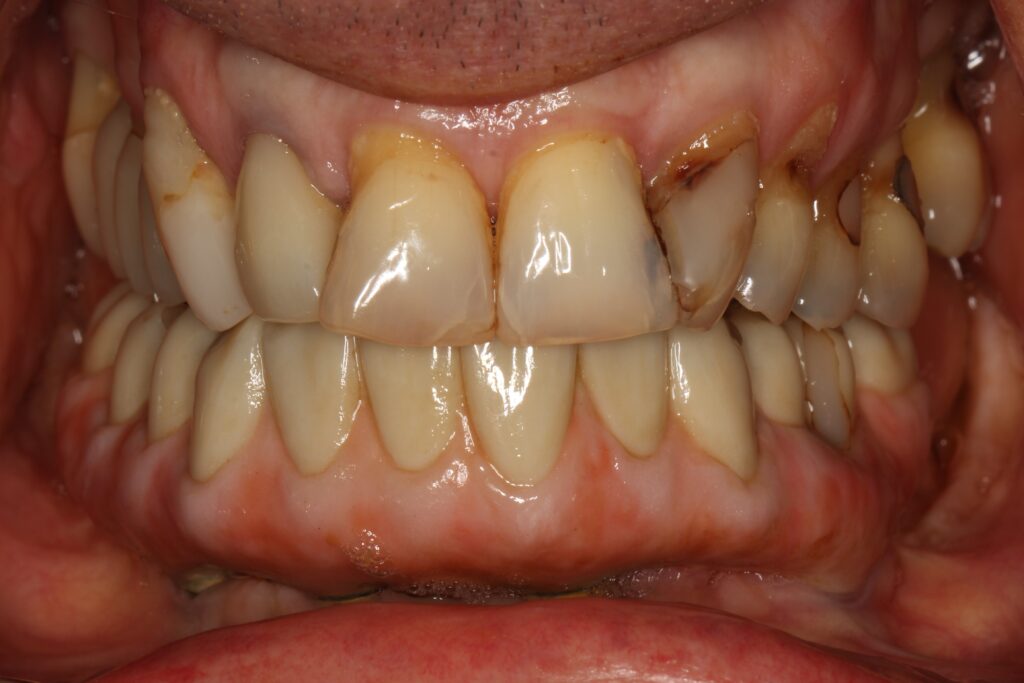

A selection of full arch fixed implant bridge patients after 5 years of wear